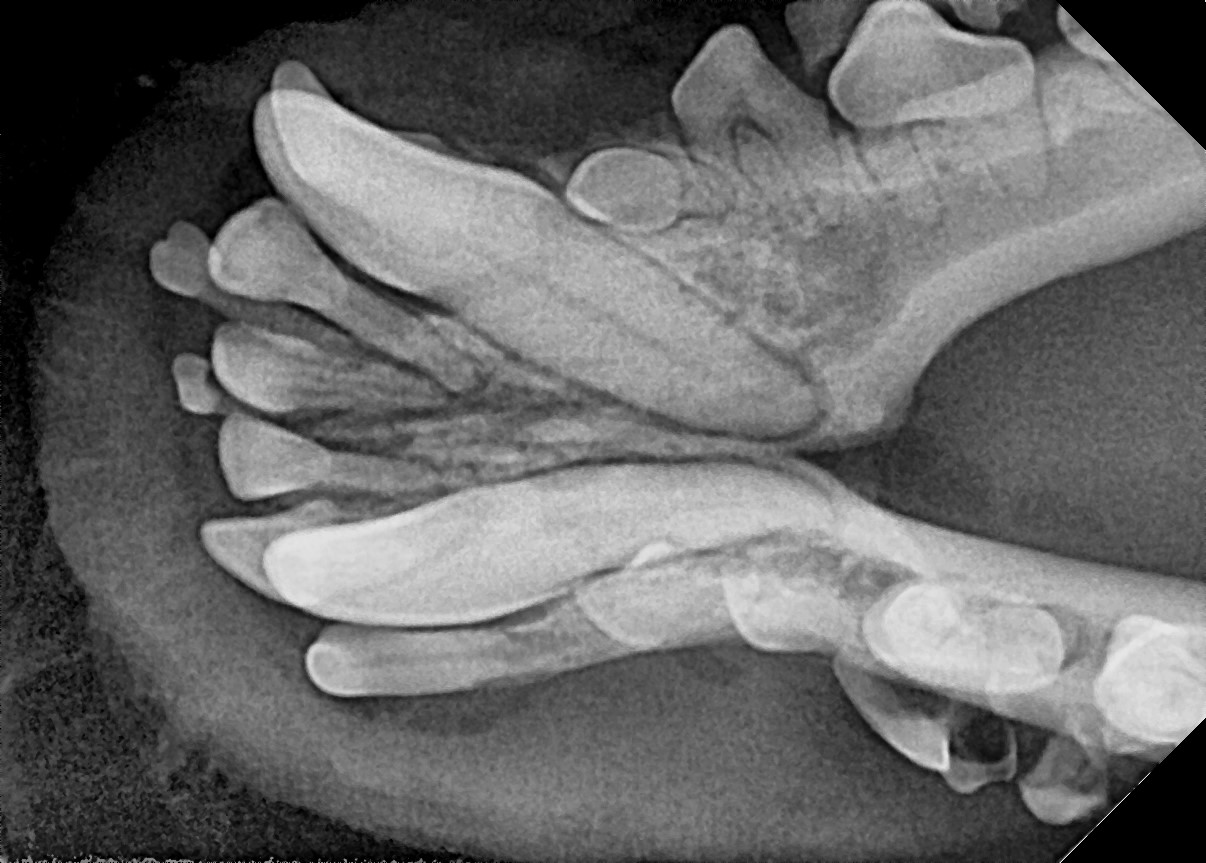

다음은 본원에 내원하여 잔존 유치를 발치한 사례입니다.

이번 사례는 송곳니 유치가 제때 빠지지 않았을 때 생길 수 있는 문제와 그 해결방법에 대하여 말씀드리고자 합니다.

잔존 유치가 탈락되지 않아 영구치가 치아 사이에 같혀 있음 위 사진은 유치가 제때 탈락되지 않아 영구치가 세 번째 앞니 아래에 갇혀 있는 것을 보여줍니다.

세 번째 앞니도 송곳니 간섭으로 인해 정상위치 보다 위쪽으로 벗어나 있는 것(deviation)을 확인할 수 있습니다.

잔존 유치를 제거해 주었더니 별다른 교정 장치를 사용하지 않았음에도 2주 후 제위치로 이동하고 있는 송곳니를 확인할 수 있습니다.